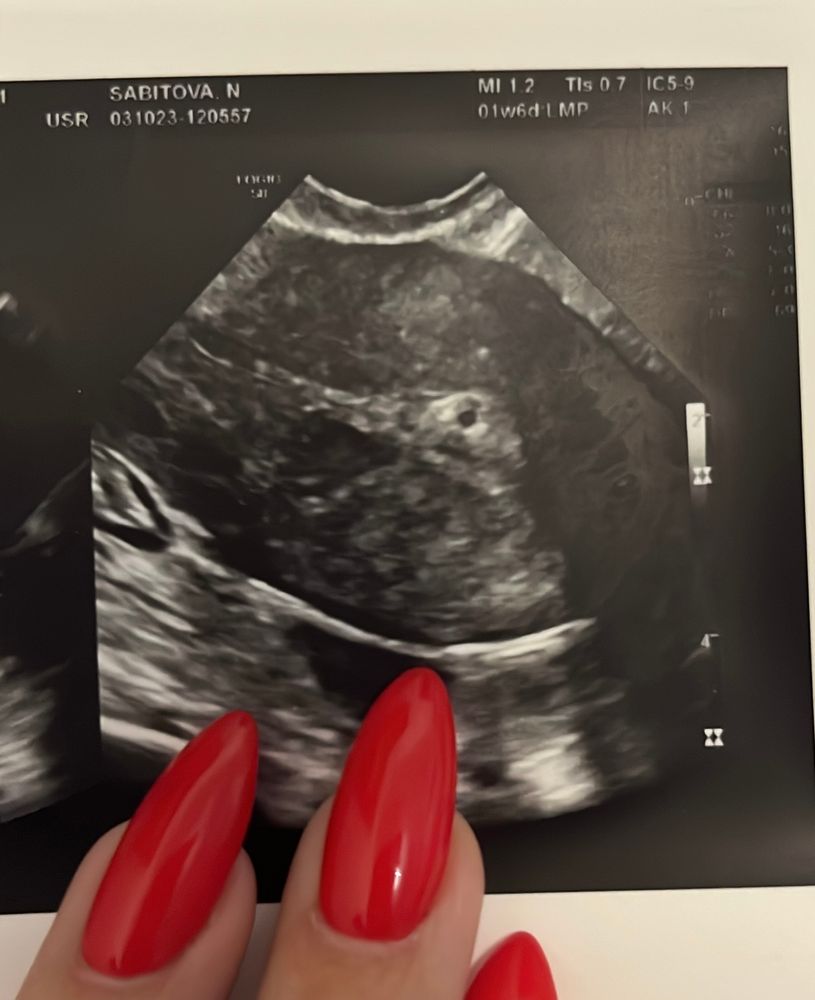

Беременность или полип ?

Арина, хчг не стала сдавать, так как тесты отрицательные. Подумала, ведь по идее, если ПЯ уже в матке, хчг должен уже вырабатываться. А тесты разных фирм отрицательные. Делаю с 3 октября каждый день. Да и такой ранней овуляции у меня никогда не было. Обычно день на 16-18. А если на 14 уже ЖТ и ПЯ в матке, то когда же была О? Это все смущает. Но два врача узи склоняются к ПЯ. Может ли быть замершая беременность?

Екатерина, вот и я так думаю, значит киста или полип? Но двух врачей узистов смущает белый ободок вокруг включения.

Провела сегодня повторное узи. Матка увеличилась, была 47*36*45, спустя 10 дней стала 52*40*54. Также анэхогенное включение. Врач даже размеры не измерила, спросила про тесты. Сказала отрицательные. Поставила под вопросом полип? Даже диагноз не прокомментировала, говорит все у врача спрашивайте. Диагноз : секретная фаза мц, признаки начальной формы аденомиоза и перенесенного эндометрита. Нельзя исключить полип. Назначила переделать узи после месячных и сдать хгч. Как то так… тесты так же отрицательные, только после высыхания что то просвечивается, наверное реагент. Врач моя ушла в отпуск, наверное жду месячных. Изображение Изображение Изображение